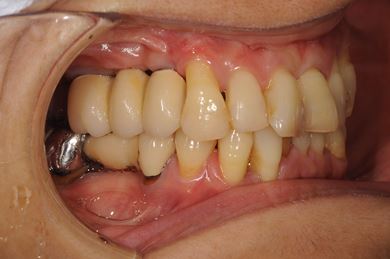

インプラントの症例写真 IMPLANT

骨再生インプラント治療

| 性別/年齢 | 女性 / 51歳 | ||||||||||||||||||||||||||||||||

| 主訴 | 他の歯科医院で入れ歯を入れたが、滑舌や味などで不自由を感じている。インプラントは難しいと言われたが、可能かどうかみていただきたい。 | ||||||||||||||||||||||||||||||||

| 治療内容 | インプラント3本(サイナスリフト)、ハイブリッドセラミッククラウン5本 | ||||||||||||||||||||||||||||||||